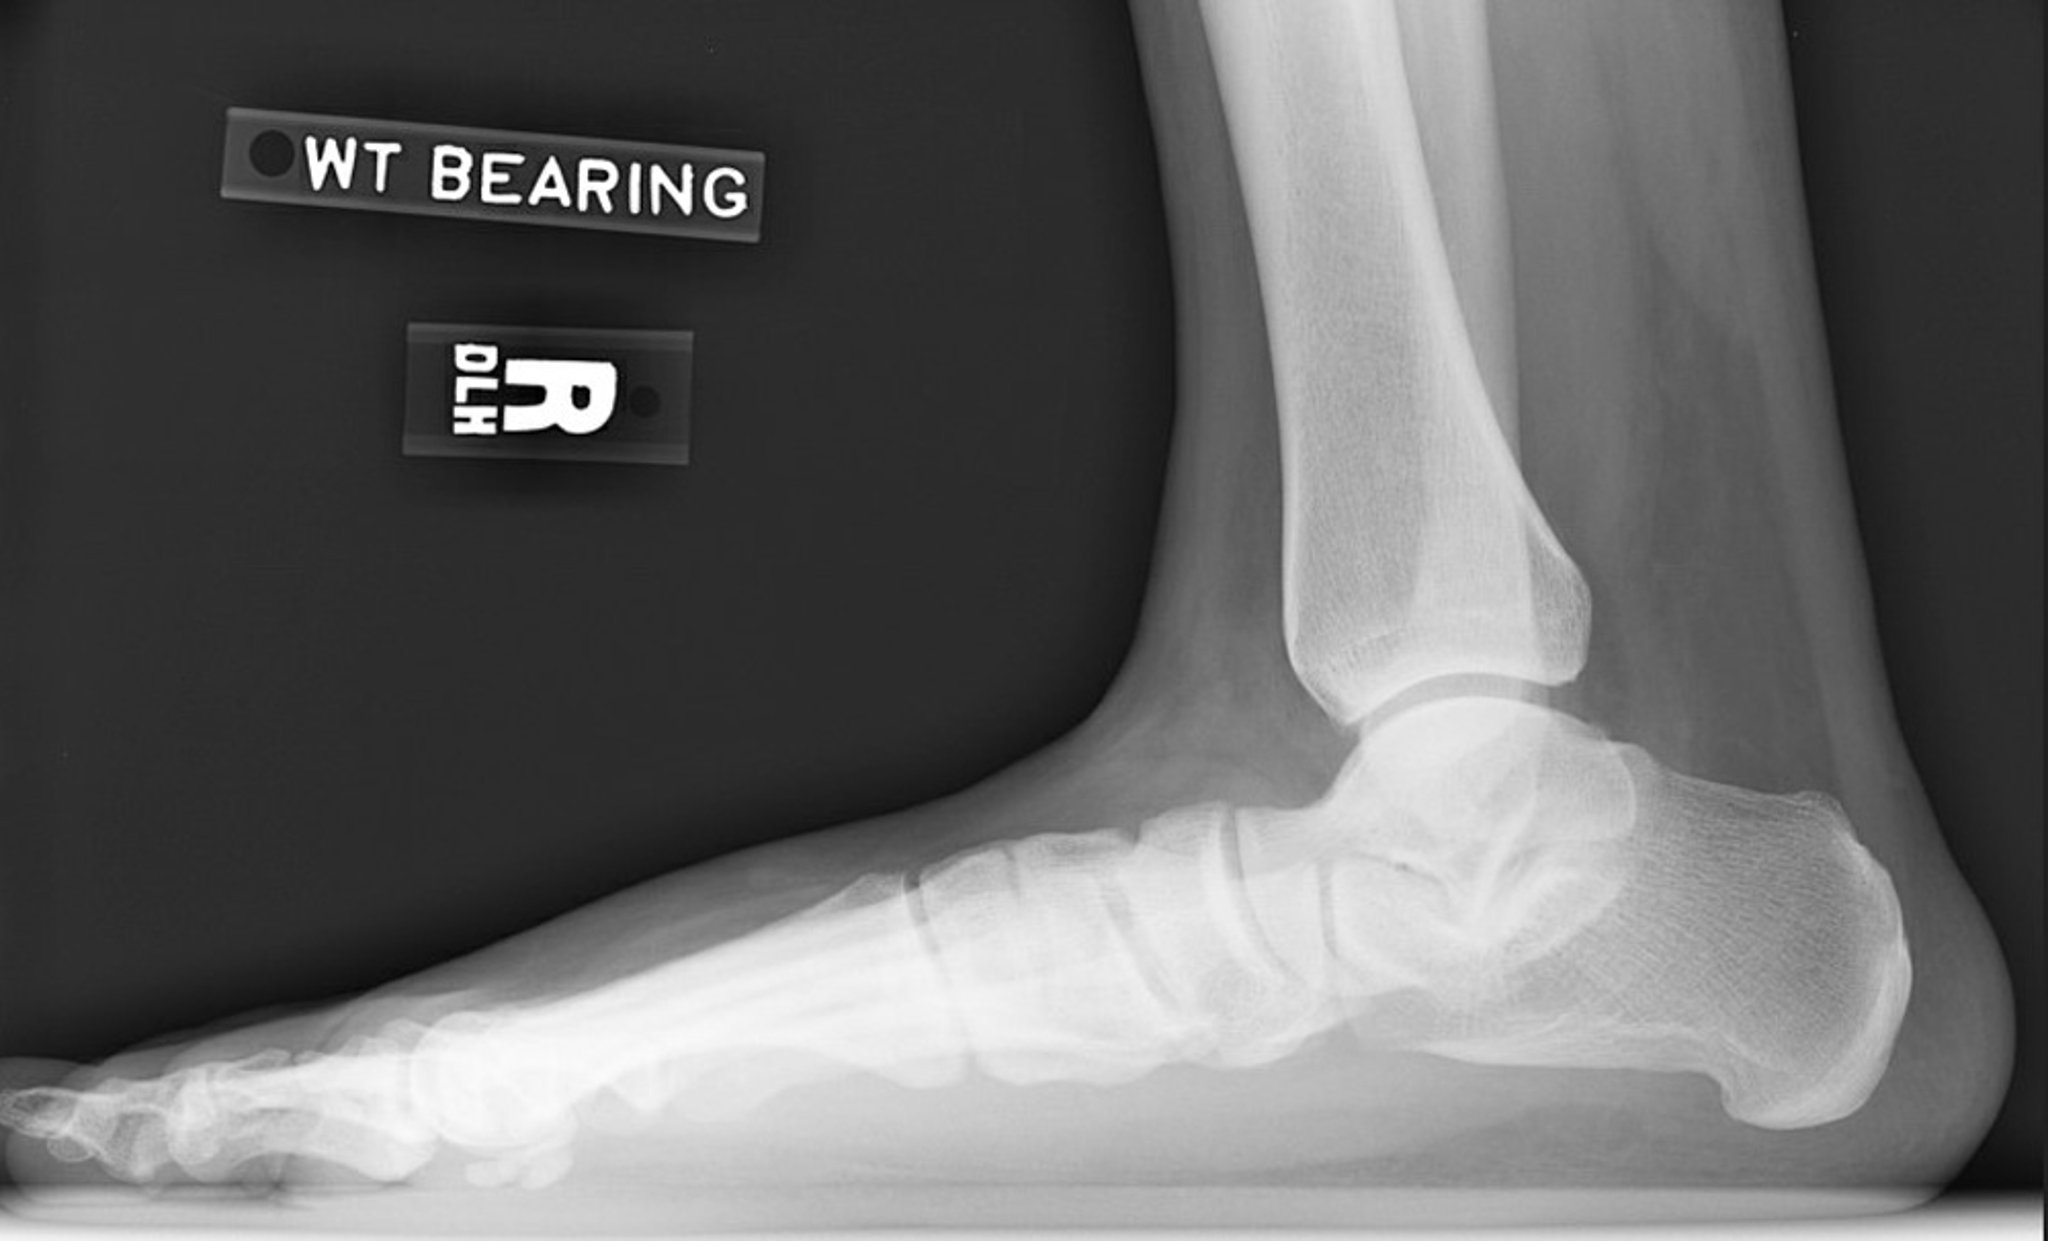

Phim X-quang bàn chân phẳng

Phim X-quang chụp nghiêng bàn chân phải cho thấy mất chiều cao vòm bàn chân. Lưu ý góc nghiêng xương gót giảm và góc nghiêng xương sên giảm. Khớp dưới sên bị thu hẹp nhưng khớp cổ chân được bảo tồn tương đối.

Hình ảnh do James C. Connors, DPM cung cấp.